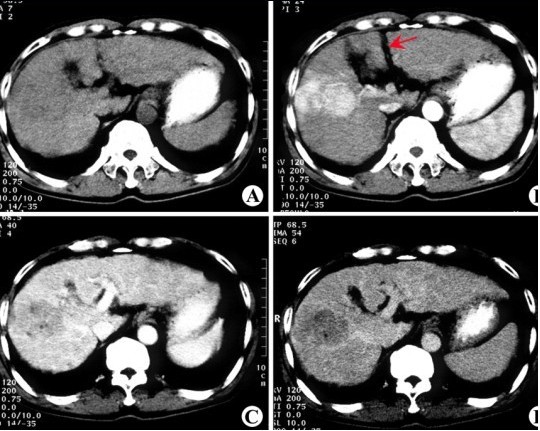

CT检查 原发性肝癌

效果:经过两个疗程结束后复查,CT示瘤体明显缩小,腹水大量减少,但并未消失。现疼痛症状有所缓解,食欲增强,体重略有增加,精神状况也有所好转。